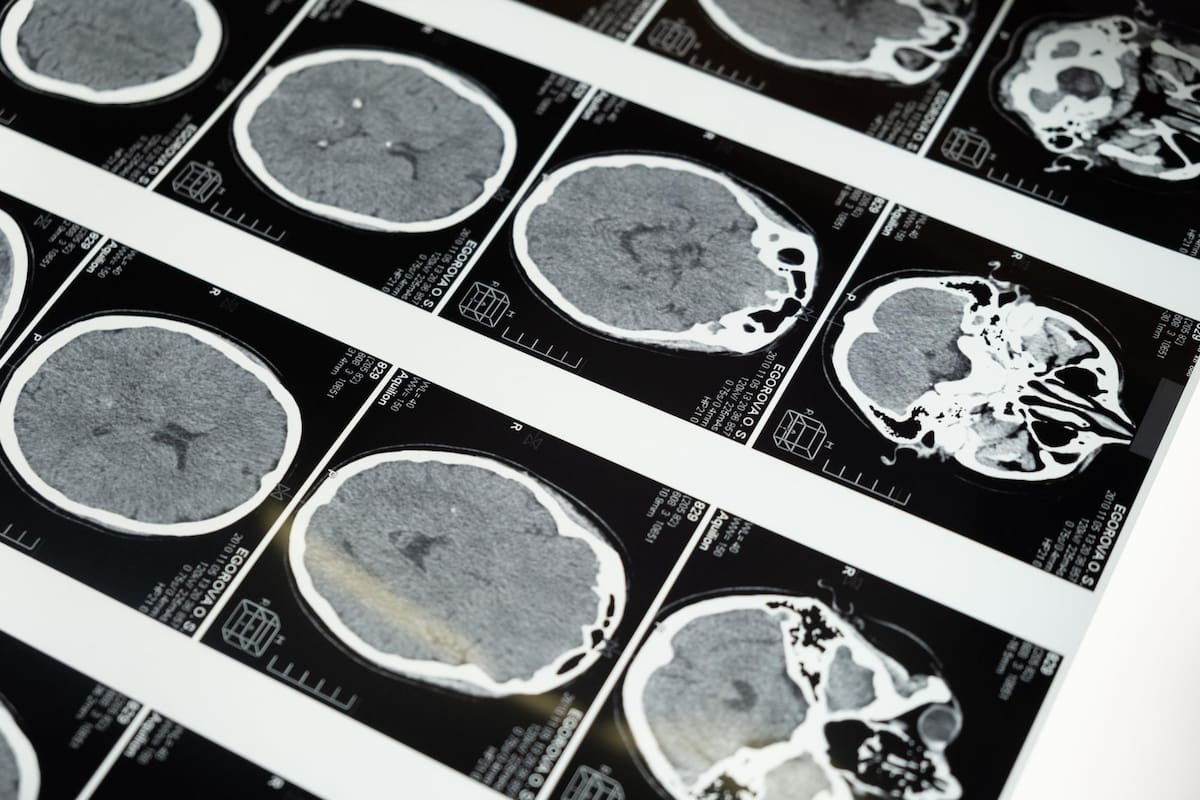

Investigaciones recientes, utilizando tecnologías avanzadas como la resonancia magnética funcional (fMRI) y la tomografía por emisión de positrones (PET), han permitido a los científicos observar el cerebro en acción. Estos estudios han revelado que ciertas habilidades cognitivas, como la memoria y la velocidad de procesamiento, pueden alcanzar su punto máximo en la edad adulta temprana, mientras que otras, como la sabiduría y la resolución de problemas prácticos, continúan desarrollándose con la experiencia acumulada a lo largo de los años.